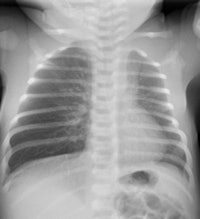

Chest x-rays and ultrasound exams are most commonly performed to diagnose and monitor treatment of newborns and young infants. Respiratory infections, both bacterial and viral, are the most common. Congenital abnormalities of the airways can cause acute respiratory problems during pulmonary infections. While x-rays are initially recommended, multidetector CT scans with multiplanar reconstructions and volume-rendering are superior in depicting the anatomy.

Viral infections are more frequent than bacterial infections in infants and may cause pneumonia. Bacterial infections are more commonly diagnosed in children age 5 and older. Chest x-ray exams are the exam of choice, although approximately 30% of children with viral infections have normal chest radiographs.